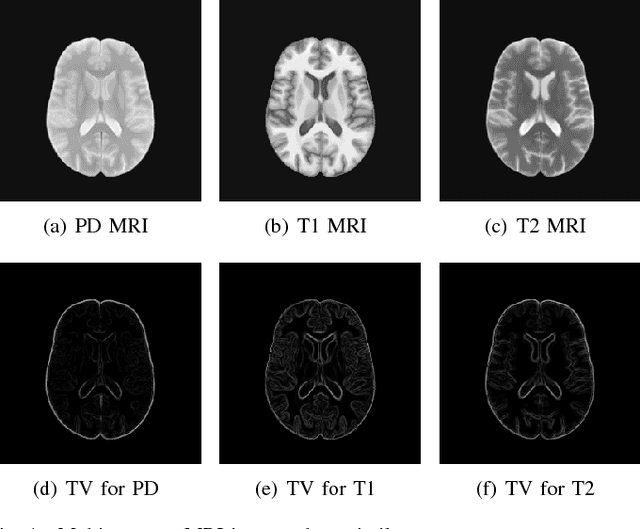

Abstract:In multi-contrast magnetic resonance imaging (MRI), compressed sensing theory can accelerate imaging by sampling fewer measurements within each contrast. The conventional optimization-based models suffer several limitations: strict assumption of shared sparse support, time-consuming optimization and "shallow" models with difficulties in encoding the rich patterns hiding in massive MRI data. In this paper, we propose the first deep learning model for multi-contrast MRI reconstruction. We achieve information sharing through feature sharing units, which significantly reduces the number of parameters. The feature sharing unit is combined with a data fidelity unit to comprise an inference block. These inference blocks are cascaded with dense connections, which allows for information transmission across different depths of the network efficiently. Our extensive experiments on various multi-contrast MRI datasets show that proposed model outperforms both state-of-the-art single-contrast and multi-contrast MRI methods in accuracy and efficiency. We show the improved reconstruction quality can bring great benefits for the later medical image analysis stage. Furthermore, the robustness of the proposed model to the non-registration environment shows its potential in real MRI applications.